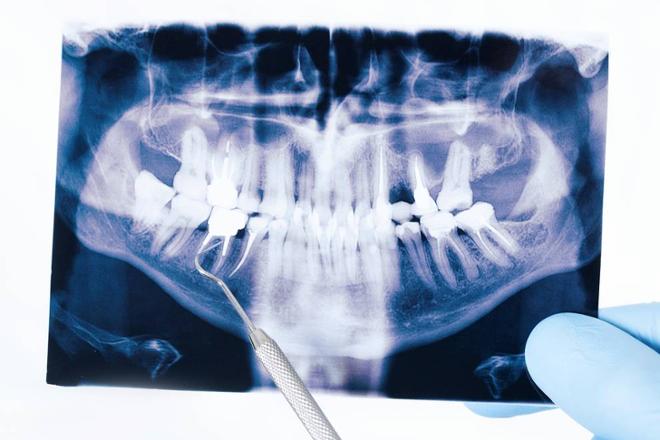

Todo sobre la extracción de muelas del juicio: tiempo de recuperación, duración de inflamación y días de reposo recomendados para una buena cicatrización.

Las muelas del juicio suelen salir antes de los 21 años y puede ser necesaria su extracción antes incluso de que erupcionen